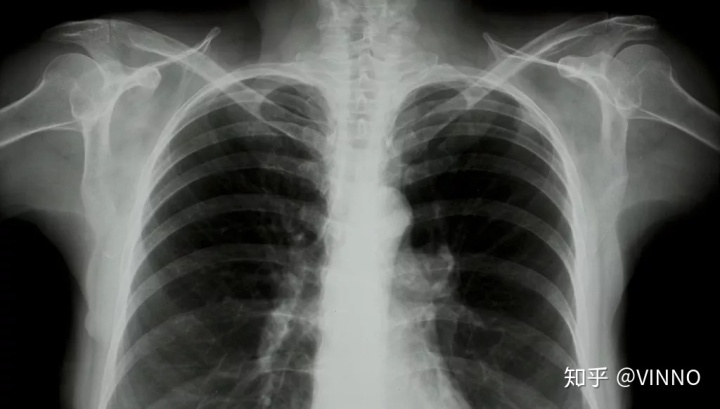

▲ 这是X光影像

成像原理:X光射线透过人体,被遮挡的部位会显示白色。X光是疾病初筛的首选检查方式,费用低廉,但影像相互重叠,组织显像不清晰,无法辨认细微结构。

胸部疾病

X光看大体、CT看细节